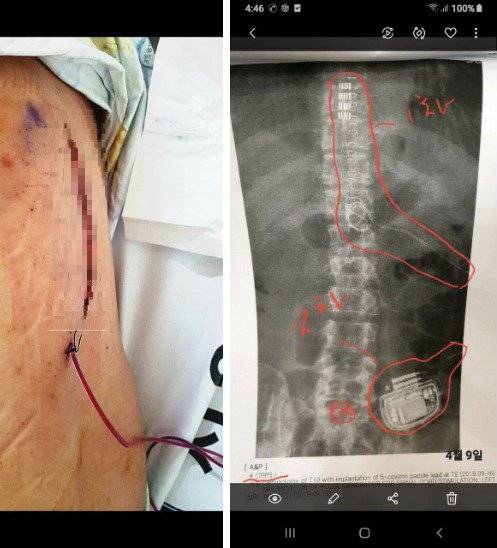

신 하사는 “휠체어 없이는 이동도 못 하고, 집 밖으로 나서기가 무섭다”고 했다. 마약성 진통제조차 듣지 않을 정도로 극심한 고통을 겪고 있기 때문이다. 급기야 몸속에 통증 조절 장치를 넣고 점검하는 대수술을 지난해 4월까지 다섯 차례나 받기도 했다.